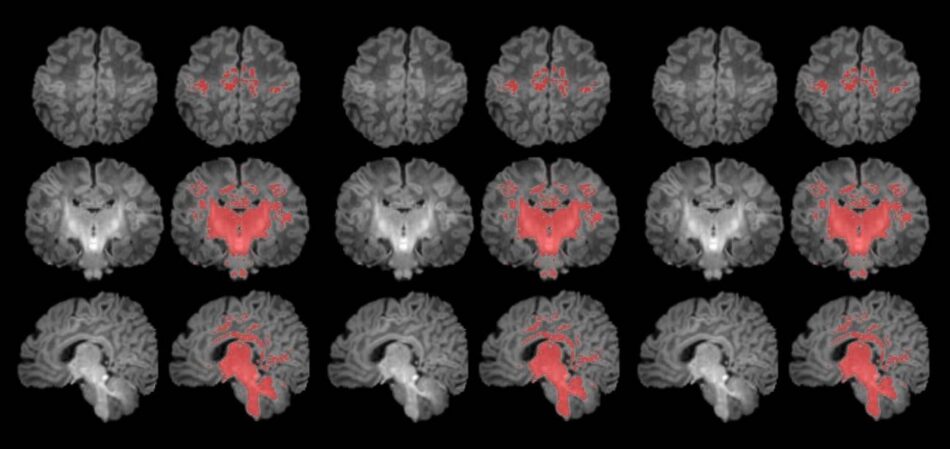

La contaminación atmosférica afecta a la maduración cerebral del bebé

Un estudio publicado en la revista Environment International concluye que la contaminación atmosférica durante el embarazo se asocia con una maduración cerebral más lenta en los recién nacidos. Se trata del primer trabajo que ha analizado en el primer mes de vida su…